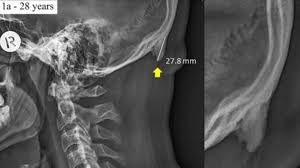

Meine Mutter war mit mir nie beim Kinderarzt weil es ein Wochenende oder Ferien waren. Feitag hat sie den Kopf noch mal abgetastet und nen Knubbel gefühlt direkt ne Einweisung ins Khs mit verdacht auf ner Zyste am Kopf oben links. Jede Beule oder Knoten sollte einem Arzt vorgestellt werden damit der einen bösartigen Tumor ausschließen kann. Da sie einen knubbel am kopf ertastete. Sie entfernen lassen bedeutet weniger Sorgen um das Kind oder Baby zu haben. Erkrankungen des kraniozervikalen Übergangs Erfahren Sie in der MSD Manuals Ausgabe für Patienten etwas über die Ursachen Symptome Diagnosen und. Betroffene bemerken oft nur einen Knubbel unter der Haut der sich prall und gummiartig anfühlt und leicht verschieben lässt. Sowieso finde ich das die Kopfseite etwas dicker war. Sie ist prall gefüllt aber eher elastisch als hart.